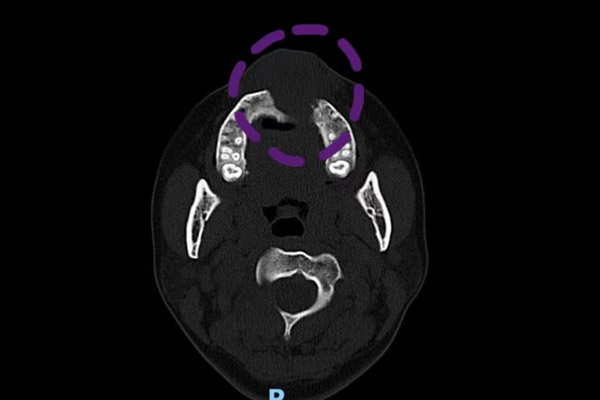

但是为了根除恶性肿瘤,切除手术是无法避免的,为了最大程度的保住患者容貌,口腔科、耳鼻咽喉科、麻醉科多学科共同商讨方案,最终决定通过多期手术的方式来达成“保脸”的目的。先进行切除手术并使用“门型”瓣修复,待患者肿瘤痊愈且无复发,再进行赝附体修复术对手术切除的骨骼进行替代。

通过科内激烈讨论,最终确定了采用下唇Abbe转移修复上唇,延长上唇,重建上唇人中处形态;两侧唇弓采用粘膜V-Y推进瓣,将口腔内粘膜推出制作红唇粘膜,并制作出赝复体,支撑面部外形,修复腭部缺损的手术方案。